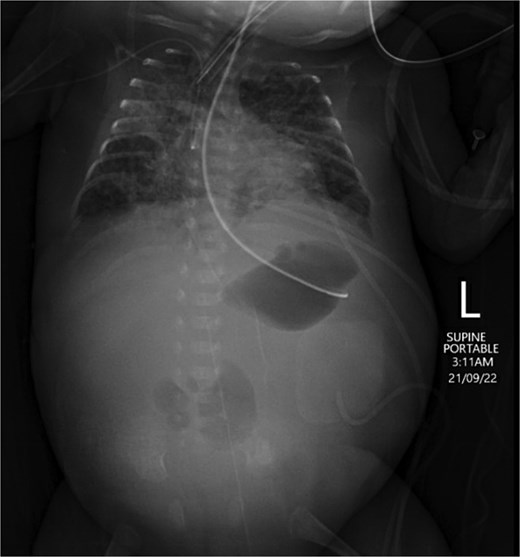

An extremely premature surviving twin baby, born at 23 weeks of gestation, was referred to our tertiary neonatal unit for advanced care. The baby weighed 560 g. He was intubated and ventilated immediately, followed by an uneventful umbilical arterial catheter and umbilical venous catheter insertion. Trophic feeds were started on Day 4 of life. Formula feeding started on Day 7. The baby passed meconium on Day 8 and abdominal distention was noted on the same day. On Day 10, the baby developed raised inflammatory markers, hyponatremia, and acidosis. The feeding was stopped, and antibiotics were started. On Day 11, he developed septic shock. Supine and lateral decubitus abdominal X-ray was done, which showed free air, confirming intestinal perforation (Fig. 1).

Supine and lateral decubitus abdominal X-rays on Day 11 of life showing free air (arrow), confirming intestinal perforation.